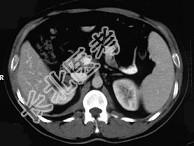

- 单项选择题女,23岁, 满月脸、向心性肥胖,CT扫描如图所示, 应诊断为 ( )

A、右侧肾上腺增生

B、右侧肾上腺腺瘤

C、右侧肾上腺腺癌

D、右侧肾上腺嗜铬细胞瘤

E、右侧肾上腺转移瘤